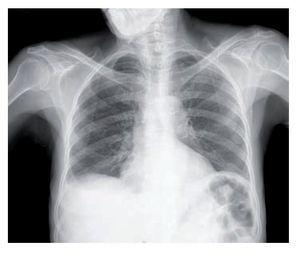

Figura 2. Tomografía axial computarizada de abdomen donde se identifica líquido libre abdominal (L) y marcado engrosamiento de la pared del antro gástrico (flecha).

Mujer de 78 años de edad que ingresó al hospital por dolor abdominal progresivo. Su padecimiento se inició 6 meses antes de su ingreso con dolor abdominal urente en epigastrio, de moderada intensidad, sin irradiación, intermitente, acompañado de saciedad temprana, plenitud posprandial, vómitos, distensión abdominal progresiva y pérdida de peso de 15 kg. Su único antecedente de importancia era un Combe positivo, pues su esposo padeció tuberculosis ganglionar 10 años antes y fue tratado con agentes antituberculosos de manera satisfactoria. A la exploración física se encontró caquéctica, con signos vitales normales, cabeza y cuello sin adenopatías, ruidos respiratorios normales sin síndrome pleuropulmonar, ruidos cardiacos normales, abdomen protuberante y globoso a expensas de líquido de ascitis, con dolor a la palpación profunda, pero sin signos de irritación peritoneal, ni hepatomegalia o esplenomegalia. En los exámenes de laboratorio la paciente presentaba anemia microcítica hipocrómica, linfopenia, hiponatremia e hipoalbuminemia. La radiografía de tórax fue normal (Figura 1). La citología del líquido de ascitis informó alteraciones inflamatorias inespecíficas y no se realizó el análisis citoquímico. La tomografía computarizada de abdomen confirmó la presencia de líquido libre abdominal y además detectó un marcado engrosamiento de la pared del estómago y del peritoneo compatible con carcinomatosis peritoneal por probable neoplasia primaria en estómago (Figura 2). Se practicó una endoscopia superior, con la que se encontró una mucosa gástrica ulcerada y friable con múltiples lesiones polipoideas que afectaban el cuerpo, antro y píloro gástricos de manera circunferencial, sin condicionar obstrucción al vaciamiento gástrico; entre las úlceras se constataron áreas de mucosa respetada y una distensibilidad gástrica disminuida (Figura 3). La biopsia de la mucosa gástrica demostró infiltrado inflamatorio granulomatoso con necrosis caseosa y células gigantes multinucleadas (Figura 4). Se practicó una tinción de Ziehl-Neelsen que resultó positiva para bacilos resistentes al ácido y al alcohol (Figura 5). Una vez obtenido el diagnóstico de tuberculosis, se inició tratamiento antifímico con base en isoniacida, rifampicina, piracinamida y etambutol por dos meses, seguido de un esquema de isoniacida y rifampicina por nueve meses adicionales, con resolución lenta y progresiva de los síntomas. La vigilancia endoscópica a los seis y nueve meses documentó una mejoría franca de las lesiones de la mucosa gástrica, y en ambas ocasiones se realizaron cultivos para Mycobacterium tuberculosis de las muestras gástricas para biopsia que dieron resultado negativo. En estos momentos la paciente se encuentra asintomática y en vigilancia clínica.